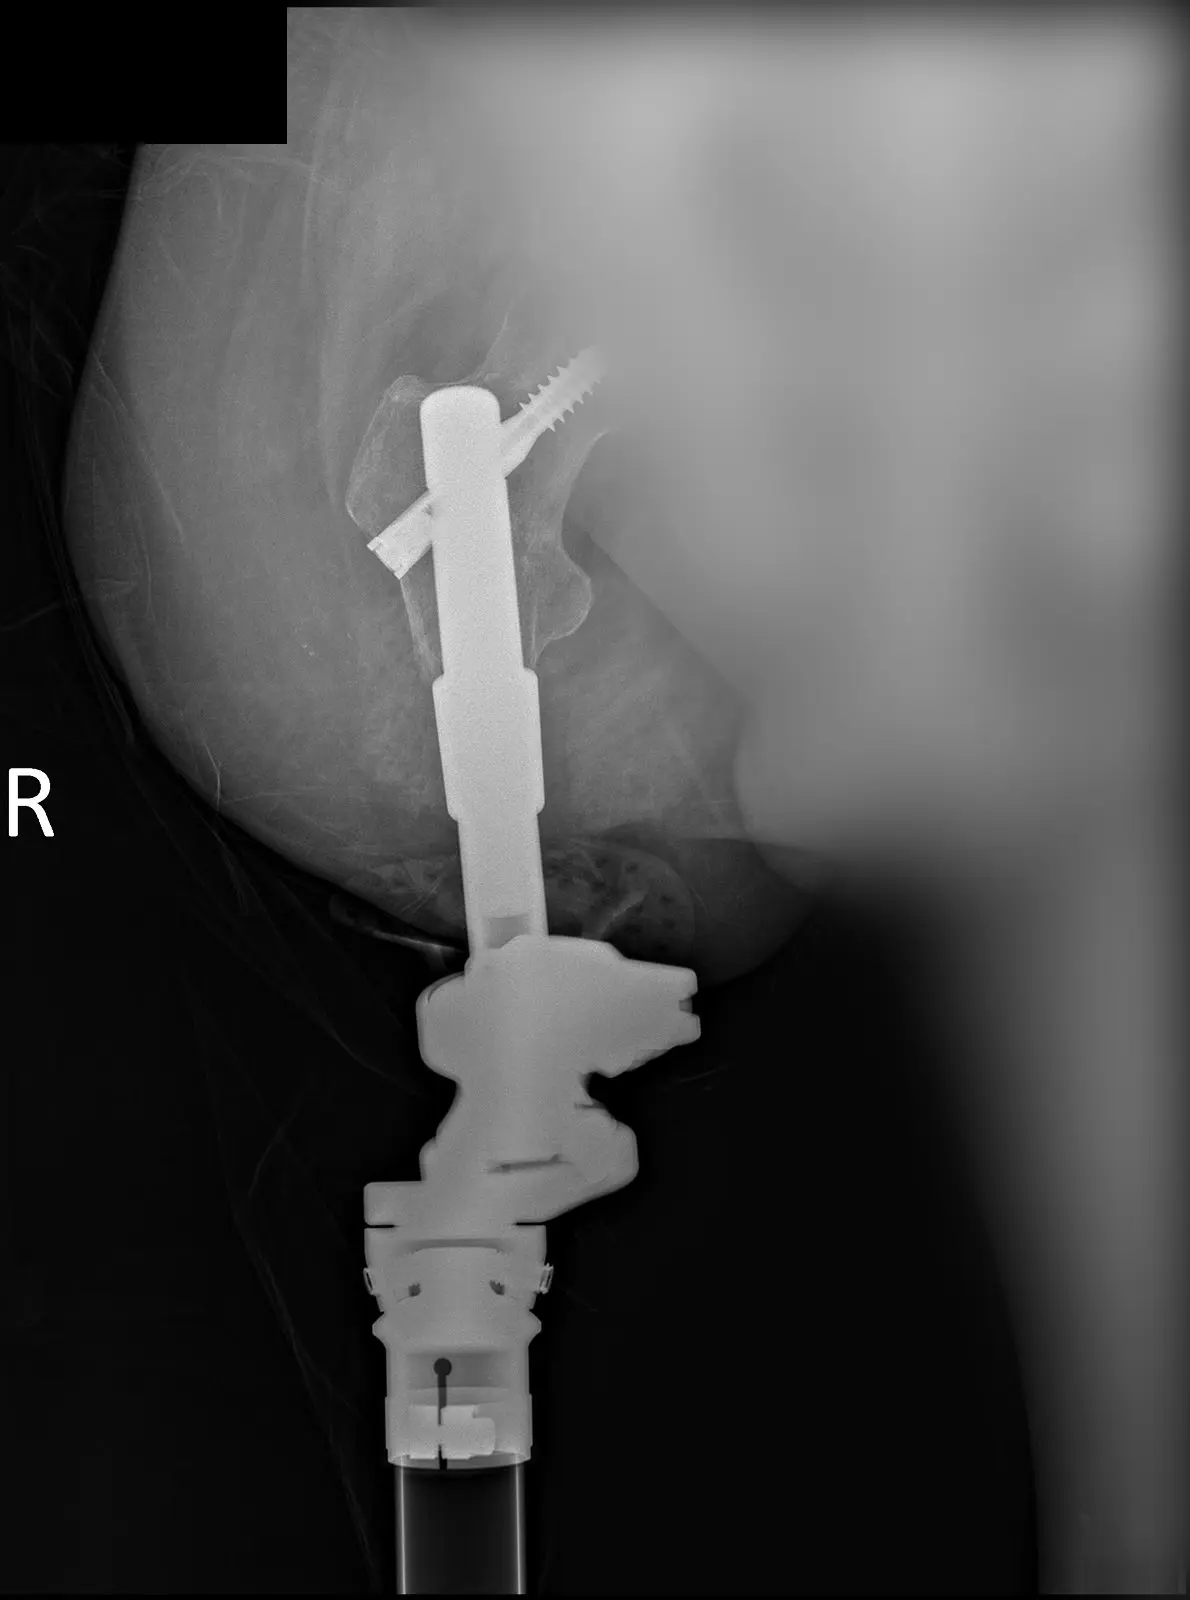

Минуло півтора місяця після проведення остеоінтегративного екзопротезування ампутованих кінцівок.

Наші хлопці впевнено рухаються вперед. Відбулася повноцінна остеоінтеграція, імплант надійно з’єднався з кісткою. Встановлені та підключені екзопротези.